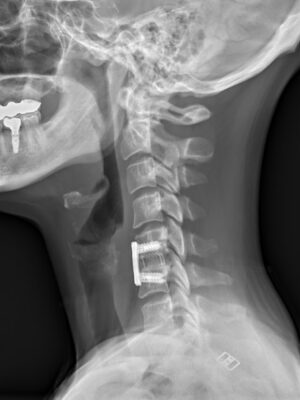

Krční páteř

Krční páteř operujeme nejčastěji z předního přístupu. Příčným řezem v tzv čárách štěpitelnosti kůže (vráskách) se dostaneme k postiženému segmentu páteře. Po odstranění meziobratlové ploténky a osteofytů, které utlačovaly nervové struktury nahradíme vyplníme meziobratlový prostor implantátem vyplněným kostním štěpem odebraným z lopaty kosti kyčelní a obratlová těla fixujeme speciální krční dlahou.

V případech víceetážového postižení krční páteře volíme operační přístup zadní.